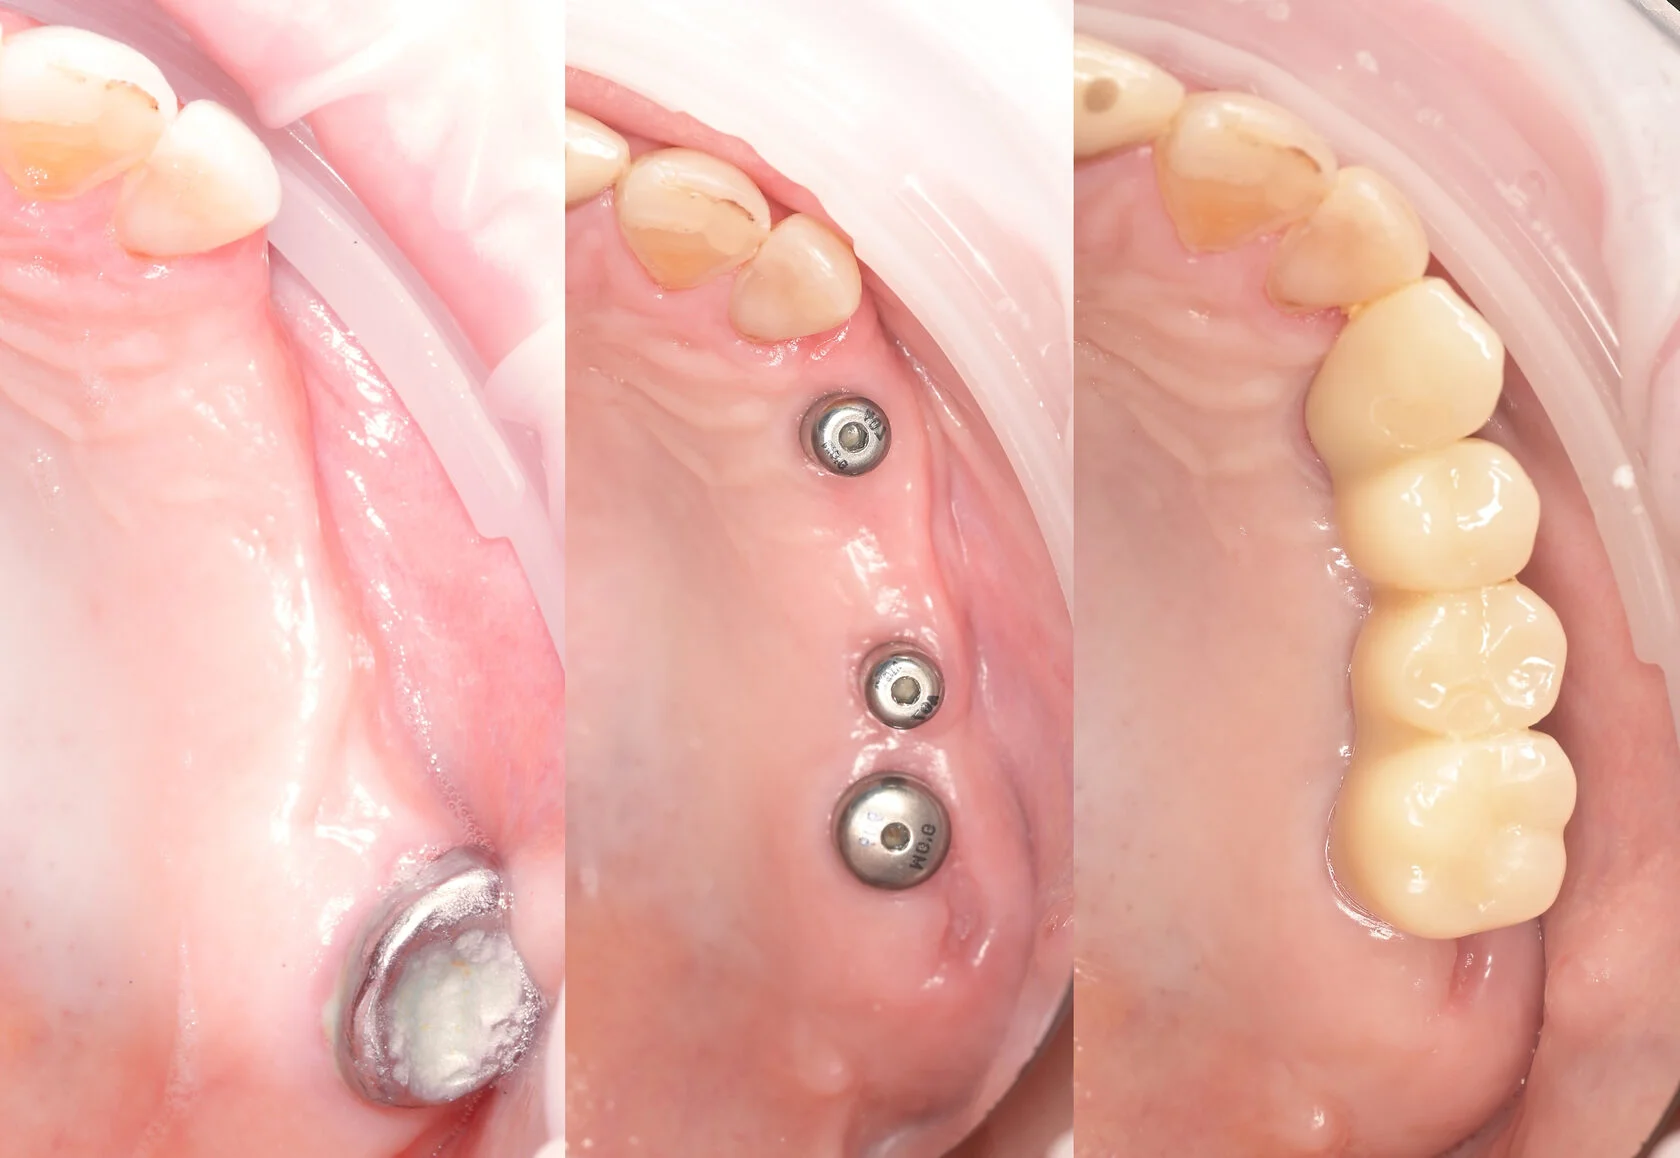

Восстановление одного или нескольких зубов с опорой на имплантаты, когда важно вернуть надёжность, комфорт и естественный внешний вид.

Пациент долго откладывал лечение, сомневаясь в необходимости серьёзного вмешательства и опасаясь сложной операции. Но со временем неудобства и ограничения в повседневной жизни, особенно во время приёма пищи, стали перевешивать сомнения.

На консультации мы подробно разобрали все этапы лечения, обсудили возможные риски и подобрали понятный и комфортный план. В итоге была проведена реабилитация верхней и нижней челюсти по концепции All-on-6 с немедленной нагрузкой. В день операции установлены имплантаты и несъёмные конструкции.

Сегодня пациент признаётся, что зря так долго сомневался — результат превзошёл его ожидания.

Долгое время откладывал лечение, потому что боялся сложной операции и долгого восстановления. Жил с постоянным дискомфортом и ограничениями в питании, но не решался сделать первый шаг. Длительное отсутствие зубов на верхней и нижней челюсти привело к потере жевательной эффективности и опоры мягких тканей.

На консультации мы подробно разобрали все этапы лечения, ответили на все вопросы и подобрали комфортный и безопасный план. По протоколу All-on-4 на обеих челюстях установлены несъёмные конструкции.

Уже в день операции пациент получил новую улыбку. Обеспечена стабильность прикуса, полноценная функция и выраженное улучшение лицевых пропорций за счёт восстановления опоры тканей.